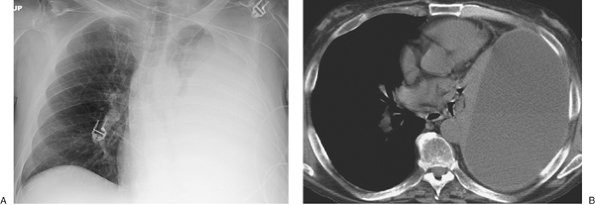

FIGURE 9-12. Re-expansion pulmonary edema. A: PA chest radiograph of a 78-year-old woman with metastatic breast cancer shows a large left pleural effusion associated with collapse of the left lung and shift of the mediastinum to the right. These findings suggest tension hydrothorax. B: PA chest radiograph after placement of a left chest tube and adequate drainage of pleural fluid shows re-expansion pulmonary edema on the left.